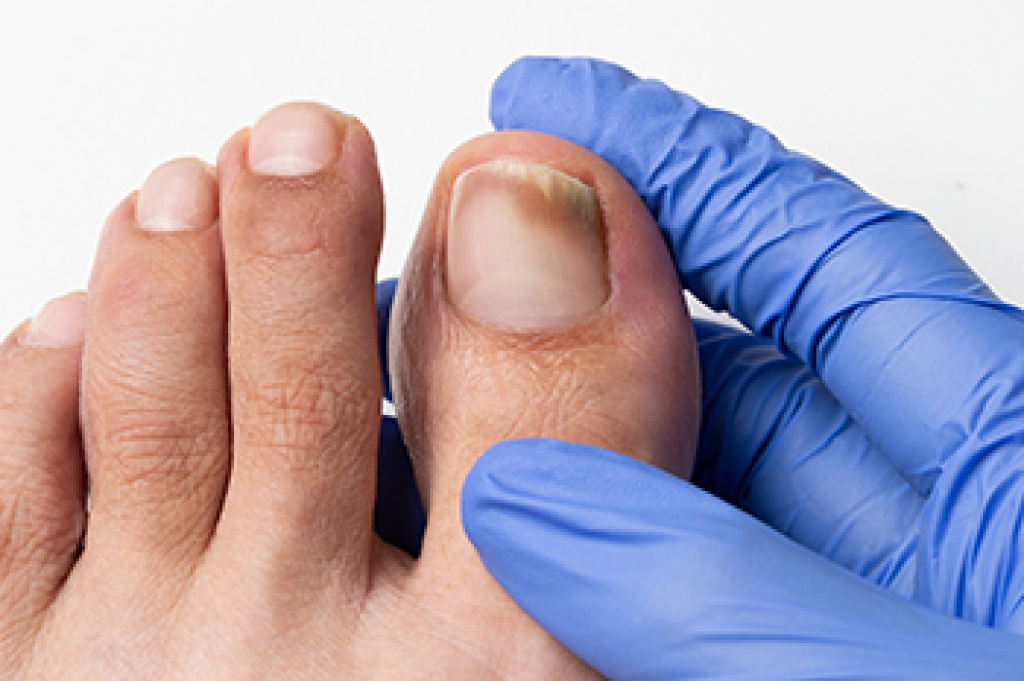

Stretching the feet is a great way to prevent injuries. If you have any concerns with your feet consult with Scott Samera, DPM from Samera / Foot + Ankle. Our doctor will assess your condition and provide you with quality foot and ankle treatment.